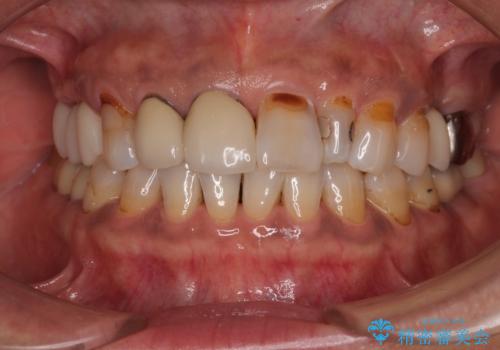

- 矮小歯である前歯がしみるとのことで来院された患者様です。

上顎前歯の歯肉ラインにエナメル質の欠損が認められ、そこが原因で冷たいものがしみている状態でした。

歯の大きさが小さいこと、隣の歯や反対側のセラミッククラウンの境目が見えていることなどから、前歯4本あるいは6本に対して、オールセラミッククラウンによる補綴治療をご提案しました。

見た目も大事だが、なるべく削りたくないとのことで、取り急ぎ4本を補綴治療し、今後犬歯の色などが気になることがあれば、追って対応することとしました。

6本同時に処置を行うと、矮小歯をより大きく見えるように工夫ができるというメリットがありましたが、4本のみの処置でも十分に満足をされていらっしゃいました。